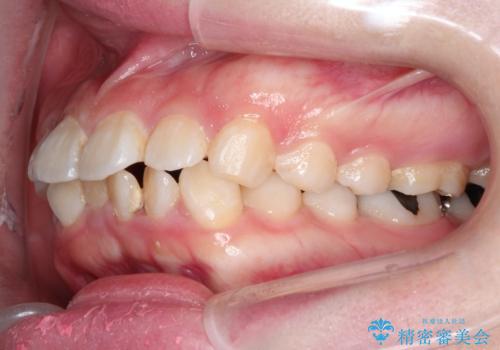

- 口元が出ていることを主訴に来院されました。

上下左右小臼歯を抜歯して審美装置で治療を行いました。

口元もスッキリと変化し、大変満足していただきました。